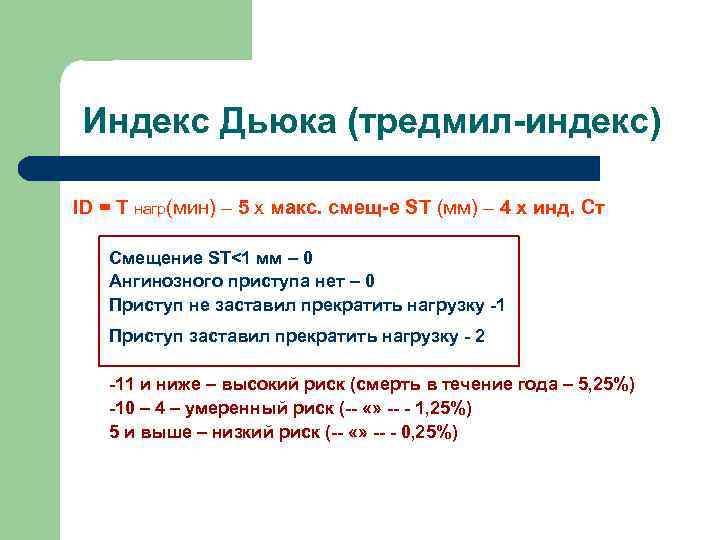

Индекс Дьюка (тредмил-индекс) ID = T нагр(мин) – 5 х макс. cмещ-е ST (мм) – 4 х инд. Ст Смещение ST<1 мм – 0 Ангинозного приступа нет – 0 Приступ не заставил прекратить нагрузку -1 Приступ заставил прекратить нагрузку - 2 -11 и ниже – высокий риск (смерть в течение года – 5, 25%) -10 – 4 – умеренный риск (-- «» -- - 1, 25%) 5 и выше – низкий риск (-- «» -- - 0, 25%)